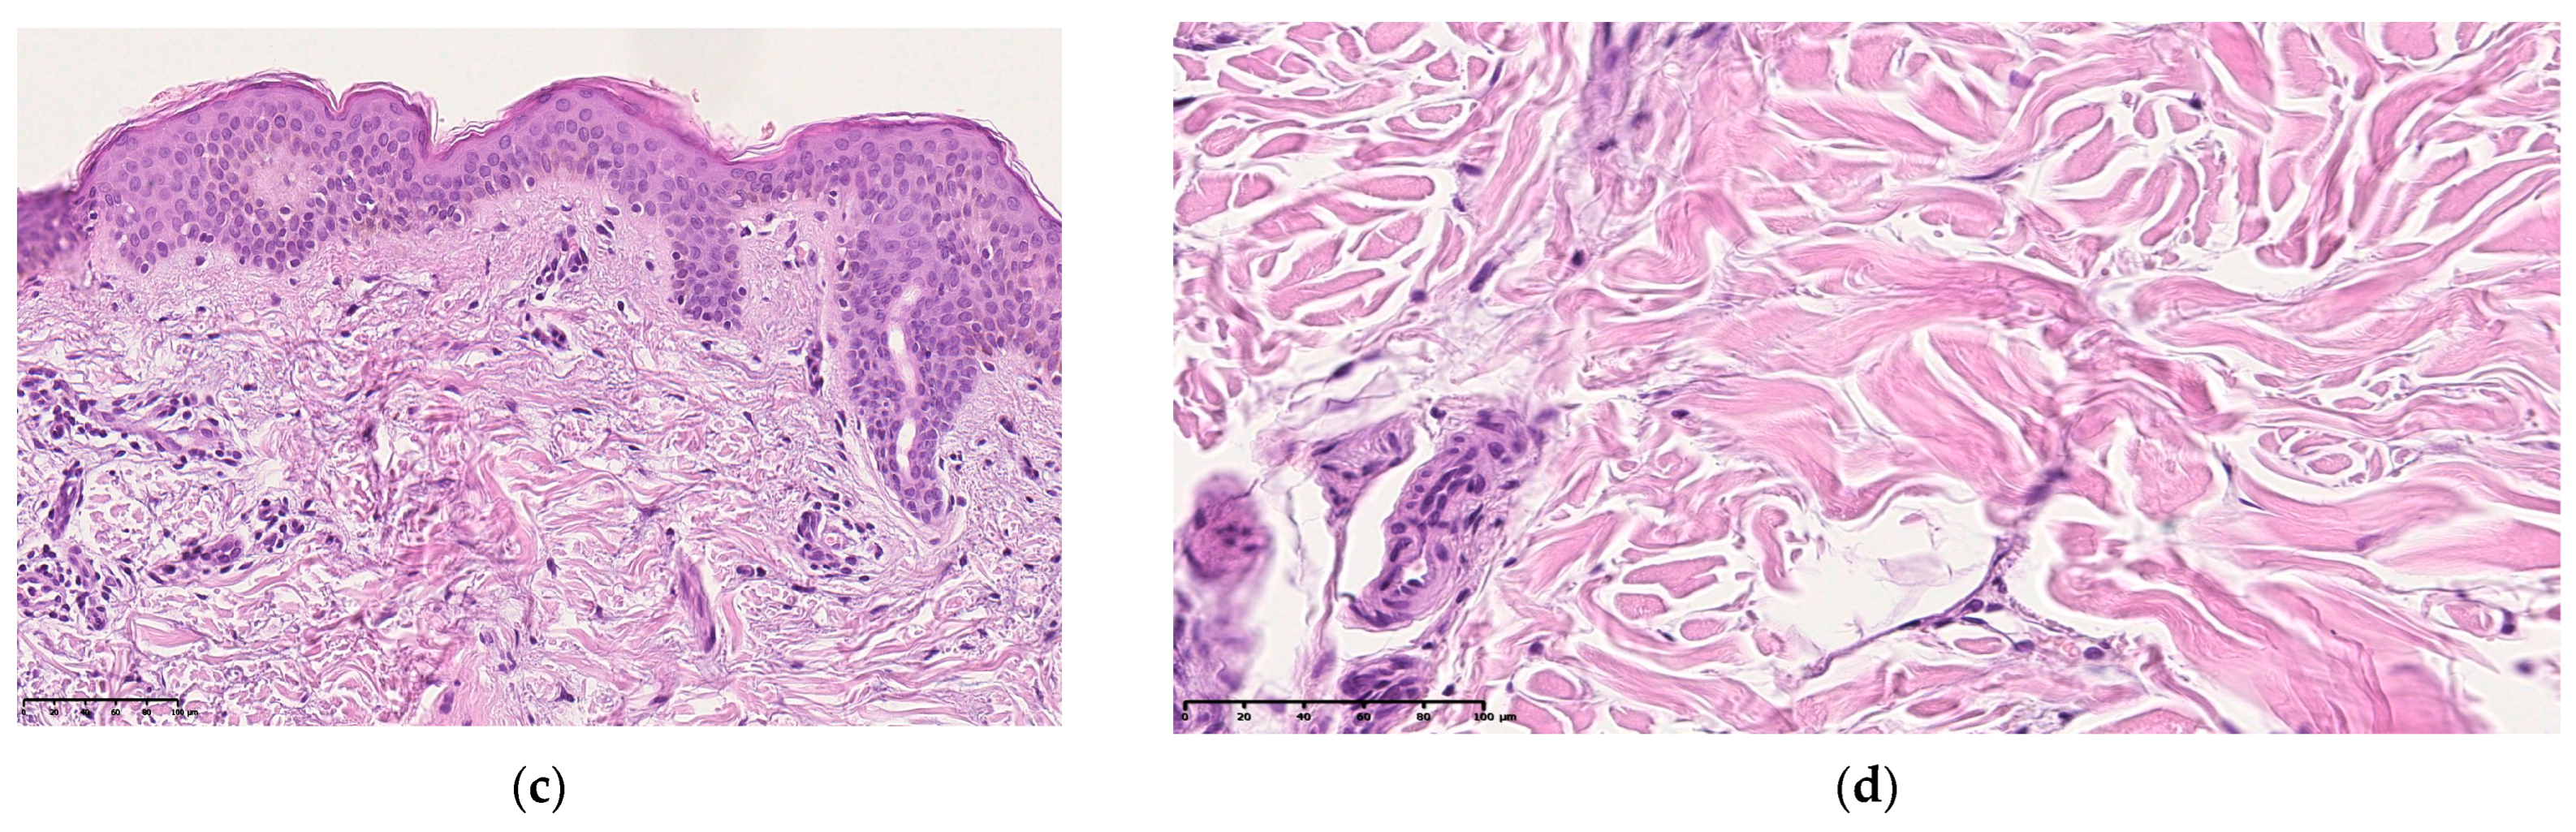

Histological examination of skin sections of patients with premature aging revealed a decrease in the thickness of the epidermis, mainly due to a decrease in the number of rows of cells of the spinous layer. The rate of keratinization of the epidermis is increased, the morphological manifestation is an increase in the thickness of the stratum corneum and its detachment from the underlying layers of the epidermis. The granular layer is weakly expressed. The undulation of the border between the papillary dermis and the epidermis is enhanced. The folding of the skin is more pronounced, the morphological manifestation of which is an increase in the height of the epidermal papillae, which look narrow and long on slices. In the papillary layer of the dermis, the fibers are thinner, the degree of their heterogeneity is pronounced, there is a decrease in the inter-fiber gaps, leading to a decrease in the thickness or its area of the papillary layer. The cell density is slightly higher than in the group of patients with normal skin aging. The border between the papillary and reticular layers of the dermis of the skin is more contrastingly pronounced (Figure 5).

Micrography of the skin section in the main group is an intact skin area of patients with premature skin aging: (a–c) stained with hematoxylin and eosin, (d,e) stained according to the Van Gieson method. ×100 (a,b,d), ×200 (c,e).

In the reticular layer, the bundles of collagen fibers are coarse and deformed, and their heterogeneity is pronounced. The area of inter-fiber gaps has been reduced.